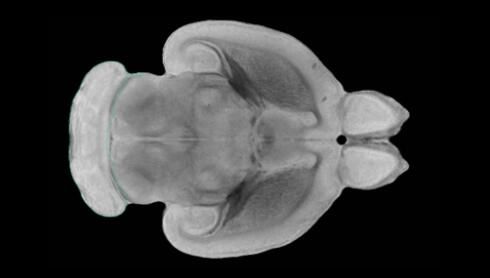

近日,一項刊登在國際雜志Nature上的研究報告中,來自劍橋大學的科學家們通過研究揭示了隨著年齡增長大腦僵硬程度的增加導(dǎo)致大腦干細胞功能異常的分子機制,同時研究者還開發(fā)出了一種新方法能將老化的干細胞逆轉(zhuǎn)回年齡健康狀態(tài);相關(guān)研究結(jié)果有望幫助研究人員理解機體大腦的老化過程以及如何開發(fā)治療年齡相關(guān)大腦疾病的新型療法。

隨著機體年齡增加,肌肉和關(guān)節(jié)都會變得僵硬,這就會使得日?;顒幼兊酶永щy,本文研究表明,我們的大腦也是如此,與年齡相關(guān)的大腦僵硬對大腦干細胞的功能或許有著重要影響。文章中,研究人員對年輕和老化大鼠的大腦進行研究闡明了年齡相關(guān)大腦僵硬對少突膠質(zhì)前體細胞(OPCs,oligodendrocyte progenitor cells)功能的影響。OPCs是一類對維持正常大腦功能非常重要的大腦干細胞,其對于髓磷脂的再生也非常重要,髓磷脂是神經(jīng)組織周圍的脂肪鞘,在多發(fā)性硬化癥中髓磷脂的再生常常會被損傷,機體老化對這些細胞的影響常常會誘發(fā)多發(fā)性硬化癥的發(fā)生,這些細胞的功能在老化的健康人群中同樣會下降。

為了確定老化OPCs的功能缺失是否可以被逆轉(zhuǎn),研究人員將來自老化大鼠機體的老化OPCs轉(zhuǎn)移到了年輕大鼠柔軟的海綿狀大腦組織中去,值得注意的是,這些老化的大腦細胞能夠重新恢復(fù)活力,其行為非常像年輕更加強壯的細胞。這項研究中,研究人員在實驗室中開發(fā)出了具有可變僵硬程度的新型材料,并在受控環(huán)境下研究這些材料的生長及其對大鼠大腦干細胞的影響,這些材料能被工程化改造具有和年齡或老化大腦相似的柔軟程度。

為了深入理解大腦組織柔軟和僵硬影響細胞行為的分子機制,研究人員對細胞表面一種名為Piezo1的蛋白質(zhì)進行了分析,該蛋白質(zhì)能“告知”細胞其周圍的環(huán)境為柔軟或僵硬。研究者Kevin Chalut說道,我們發(fā)現(xiàn),當在僵硬材料上促進年輕具有功能性的大鼠干細胞時,這些細胞就會表現(xiàn)出功能異常,并失去其再生的能力,實際上其行為與老化細胞相似。當將老化的大腦細胞在柔軟材料上生長時,其功能就會表現(xiàn)得像年輕細胞一樣,換句話說,其能夠重新恢復(fù)年輕的活力。

當研究者從老化大腦干細胞的表面剔除Piezo1蛋白后,他們就能夠誘騙細胞感知柔軟的周圍環(huán)境,甚至當將細胞在僵硬材料上生長時也是如此。此外,當在老化大鼠大腦中剔除OPCs上的Piezo1時,就會促進細胞變得年輕并再次承擔正常的再生功能。研究者Susan Kohlhaas表示,多發(fā)性硬化癥是一種痛苦讓患者致殘的疾病,隨著時間推移,我們迫切需要開發(fā)出減緩并抑制患者殘疾的新型療法。這項研究中,研究人員闡明了大腦干細胞老化的分子機制,以及如何通過逆轉(zhuǎn)該過程來實現(xiàn)恢復(fù)大腦干細胞活力,后期研究人員將會基于本文研究開發(fā)出新型療法來治療多種與老化和多發(fā)性硬化癥相關(guān)的疾病,包括如何潛在恢復(fù)大腦失去的功能等。